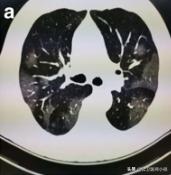

肺实变吸收后“融化的糖”样改变

肺部好转

如果患者得到有效的治疗,或者患者症状较轻免疫力成功抵御了病毒,炎症将进一步吸收程度开始降低。

开始恢复的肺